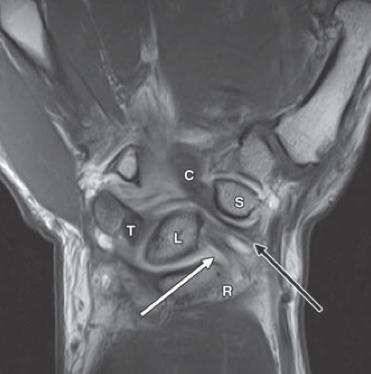

앞쪽의 경우 Radius 와 Ulna 와 수근골을 연결하는 단단한 인대들이 구성되어 있고

RSC 는 손목 안정화에 주요한 구조물 입니다. (Proximal row carpectomy 후에도 살리는 구조물 입니다.)

없으면 척골쪽으로 수근골들이 모두 빠지기 쉽습니다.